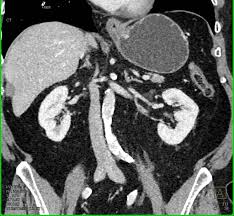

Contrast Enhanced Ct Scan Taken At Two Levels Through The Kidneys A Download Scientific Diagram

Renal Sarcoidosis Mimicking Xanthogranulomatous Pyelonephritis Urology